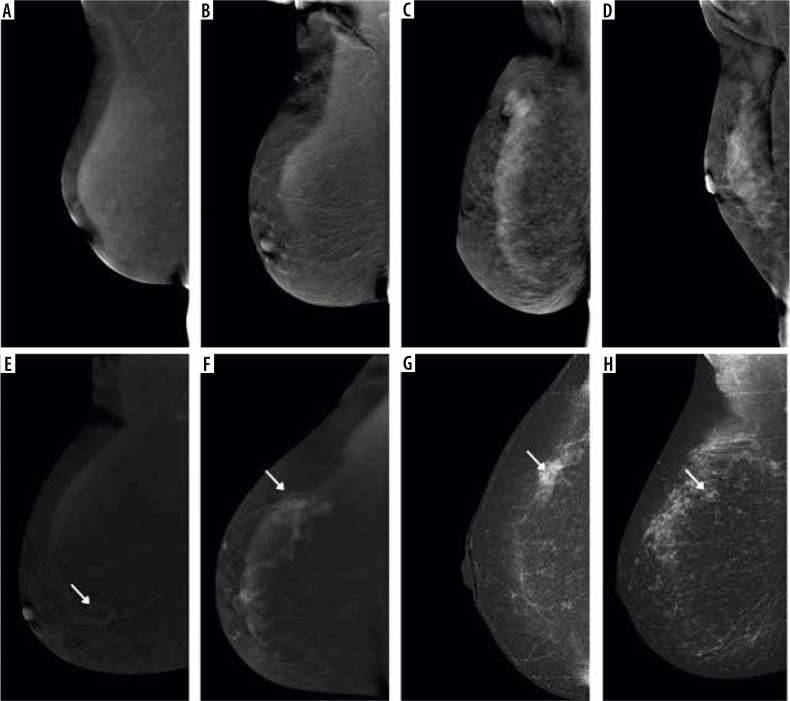

Purpose: To assess the effectiveness of contrast-enhanced mammography (CEM) recombinant images in detecting malignant lesions in patients with extremely dense breasts compared to the all-densities population.

Material and methods: 792 patients with 808 breast lesions, in whom the final decision on core-needle biopsy was made based on CEM, and who received the result of histopathological examination, were qualified for a single-centre, retrospective study. Patient electronic records and imaging examinations were reviewed to establish demographics, clinical and imaging findings, and histopathology results. The CEM images were reassessed and assigned to the appropriate American College of Radiology (ACR) density categories.

Results: Extremely dense breasts were present in 86 (10.9%) patients. Histopathological examination confirmed the presence of malignant lesions in 52.6% of cases in the entire group of patients and 43% in the group of extremely dense breasts. CEM incorrectly classified the lesion as false negative in 16/425 (3.8%) cases for the whole group, and in 1/37 (2.7%) cases for extremely dense breasts. The sensitivity of CEM for the group of all patients was 96.2%, specificity - 60%, positive predictive values (PPV) - 72.8%, and negative predictive values (NPV) - 93.5%. In the group of patients with extremely dense breasts, the sensitivity of the method was 97.3%, specificity - 59.2%, PPV - 64.3%, and NPV - 96.7%.

Conclusions: CEM is characterised by high sensitivity and NPV in detecting malignant lesions regardless of the type of breast density. In patients with extremely dense breasts, CEM could serve as a complementary or additional examination in the absence or low availability of MRI.